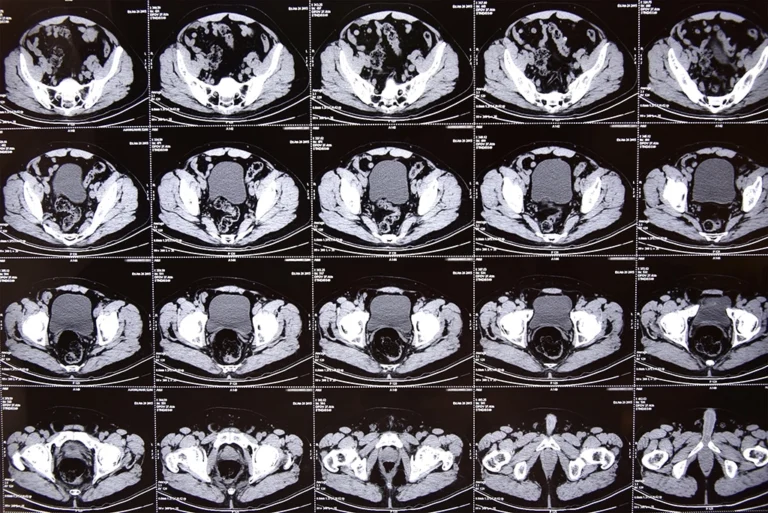

A pelvic CT scan uses x-ray technology to take multiple images of the pelvic region, creating 3-D images from all different angles, so that any abnormal growth or abnormal tissue will appear as a distinct image on the scan. Areas seen on the scan typically include lymph nodes, bladder, and prostate, as well as other areas of the abdomen that could be affected.

A pelvic CT scan provides detailed images of the soft tissues and organs in the pelvic area. The size, shape, location, and extent of any abnormal growth or tumor within soft tissues or organs will be clearly seen on the scan.

Tumors will look different from healthy tissue on the scan, and an organ may look unusual in its shape or size, which could suggest a tumor is present.